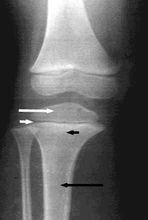

乾骺端發育不良(Pyle病)是一種罕見的常染色體隱性遺傳性疾病,常常在名稱上與顱骨幹骺端發育不良相混淆(見下文).受累患者除了外翻膝畸形外,臨床表現正常,但是偶爾會發生脊柱側凸和骨骼變脆。常常是由於其他的原因作X線檢查時偶然發現。